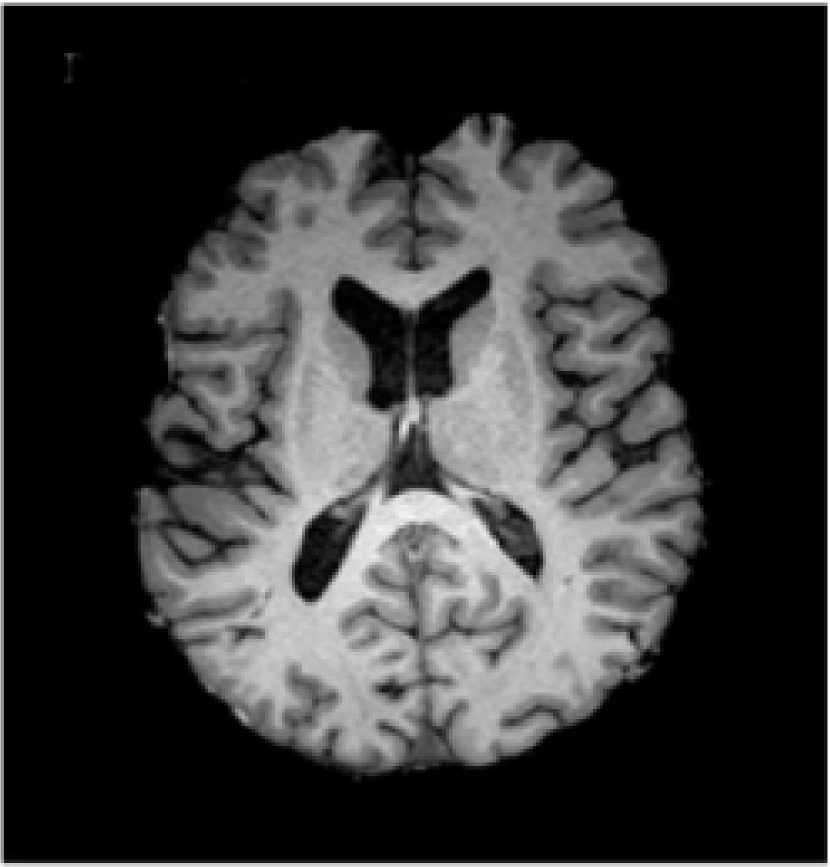

Acquired brain MRI volumes incorporate non-brain tissue parts of the head, such as eyes, fat, spinal cord or skull. The process of extracting the brain tissue from non-brain one is referred in the literature as skull stripping. An example of an original volume and its corresponding skull stripped output is presented in Fig. 4(a) and  4(b), respectively. This step has direct consequences on the performance of automated methods, as the inclusion of skull or eyes as brain tissue may lead to unexpected results in classification [102, 103], while unintended removal of the cortical surface may result in underestimation of the cortical thickness [104]. Among the different methods proposed in the literature for skull-stripping [105, 102, 106], methods such as BET [107, 108], BSE [109], ROBEX [110] and BEaST [111] are commonly used. In the literature, the methods used in clinical trail datasets employed BET [21, 25, 112] and ROBEX [23]. Zhang et al[26] applied a paediatric brain skull stripping algorithm known as LABEL [113]. The public dataset images from the Brain Tumor Image Segmentation Challenge (BRATS) 2013222http://martinos.org/qtim/miccai2013/, 2014333https://sites.google.com/site/miccaibrats2014/ and 2015444https://www.smir.ch/BRATS/Start2015 are preprocessed in this regard beforehand.

Refer to caption

(a) T1-w image

(b) Skull stripped

Figure 4: An example of two preprocessing methods: skull stripping and bias field correction [114]. In the figure, a T1-w slice is displayed in (a), brain tissue after removing non-brain areas in (b), estimated bias field in (c), and preprocessed brain tissue in (d).